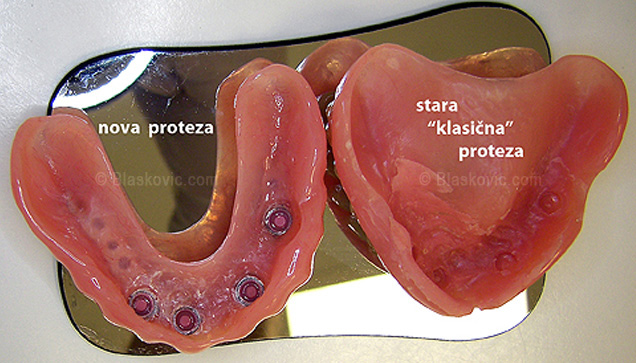

4. Proteze nad implantatima

Proteza učvršćena implantatima predstavlja, u stvari, "mobilni most". Radi se o jeftinijem protetskom rješenju gdje je oralnu higijenu puno lakše održavati. Ipak cementirani most nad implantatima je svakako kvalitetnije rješenje.